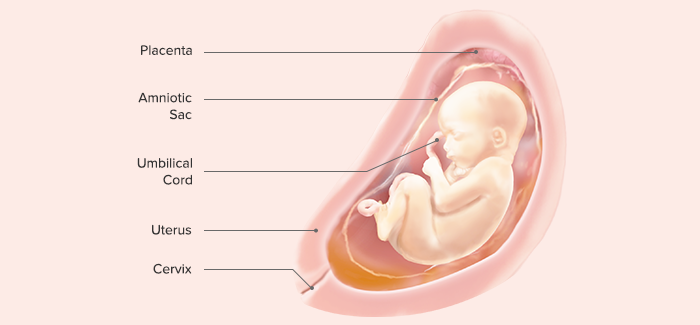

The placenta (Latin for “pancake,” which is descriptive of its size and appearance at term) arises out of the continuing growth of trophoblast tissue. Its growth parallels that of the fetus, growing from a few identifiable cells at the beginning of pregnancy to an organ 15 to 20 cm in diameter and 2 to 3 cm in-depth, covering about half the surface area of the internal uterus at term.

C. The Amniotic Membranes

D. The Amniotic Fluid

E. The Umbilical Cord

The umbilical cord is formed from the fetal membranes (amnion and chorion) and provides a circulatory pathway that connects the embryo to the chorionic villi of the placenta. Its function is to transport oxygen and nutrients to the fetus from the placenta and to return waste products from the fetus to the placenta. It is about 53 cm (21 in) in length at term and about 2 cm (3 ⁄4 in) thick. The bulk of the cord is a gelatinous mucopolysaccharide called Wharton’s jelly, which gives the cord body and prevents pressure on the vein and arteries that pass through it. The outer surface is covered with amniotic membrane.

III. End of 12th Gestational Week (First Trimester)

Length: 7–8 cm

Weight: 45 g

Nail beds are forming on fingers and toes.

Spontaneous movements are possible, although they are usually too faint to be felt by the mother.

Some reflexes, such as the Babinski reflex, are present.

Bone ossification centers begin to form.

Tooth buds are present.

Sex is distinguishable by outward appearance.

Urine secretion begins but may not yet be evident in amniotic fluid.

The heartbeat is audible through Doppler technology.